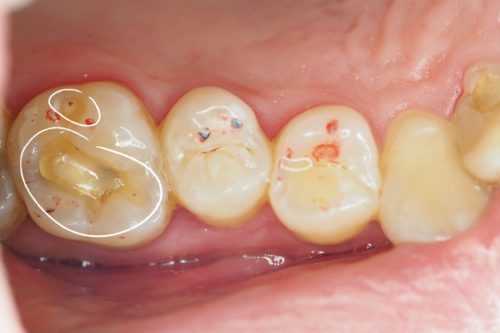

Pacjentka zgłosiła się z powodu nieestetycznego przebarwienia pomiędzy zębami, w okolicy obecnego wypełnienia

Usunięto nieszczelne wypełnienia, całkowicie opracowano ubytki próchnicowe i założono dopasowane kolorem i przeziernością wypełnienia kompozytowe